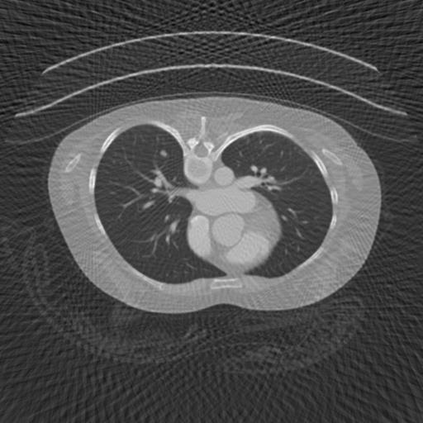

Sparse-view computed tomography (CT) -- using a small number of projections for tomographic reconstruction -- enables much lower radiation dose to patients and accelerated data acquisition. The reconstructed images, however, suffer from strong artifacts, greatly limiting their diagnostic value. Current trends for sparse-view CT turn to the raw data for better information recovery. The resultant dual-domain methods, nonetheless, suffer from secondary artifacts, especially in ultra-sparse view scenarios, and their generalization to other scanners/protocols is greatly limited. A crucial question arises: have the image post-processing methods reached the limit? Our answer is not yet. In this paper, we stick to image post-processing methods due to great flexibility and propose global representation (GloRe) distillation framework for sparse-view CT, termed GloReDi. First, we propose to learn GloRe with Fourier convolution, so each element in GloRe has an image-wide receptive field. Second, unlike methods that only use the full-view images for supervision, we propose to distill GloRe from intermediate-view reconstructed images that are readily available but not explored in previous literature. The success of GloRe distillation is attributed to two key components: representation directional distillation to align the GloRe directions, and band-pass-specific contrastive distillation to gain clinically important details. Extensive experiments demonstrate the superiority of the proposed GloReDi over the state-of-the-art methods, including dual-domain ones. The source code is available at https://github.com/longzilicart/GloReDi.